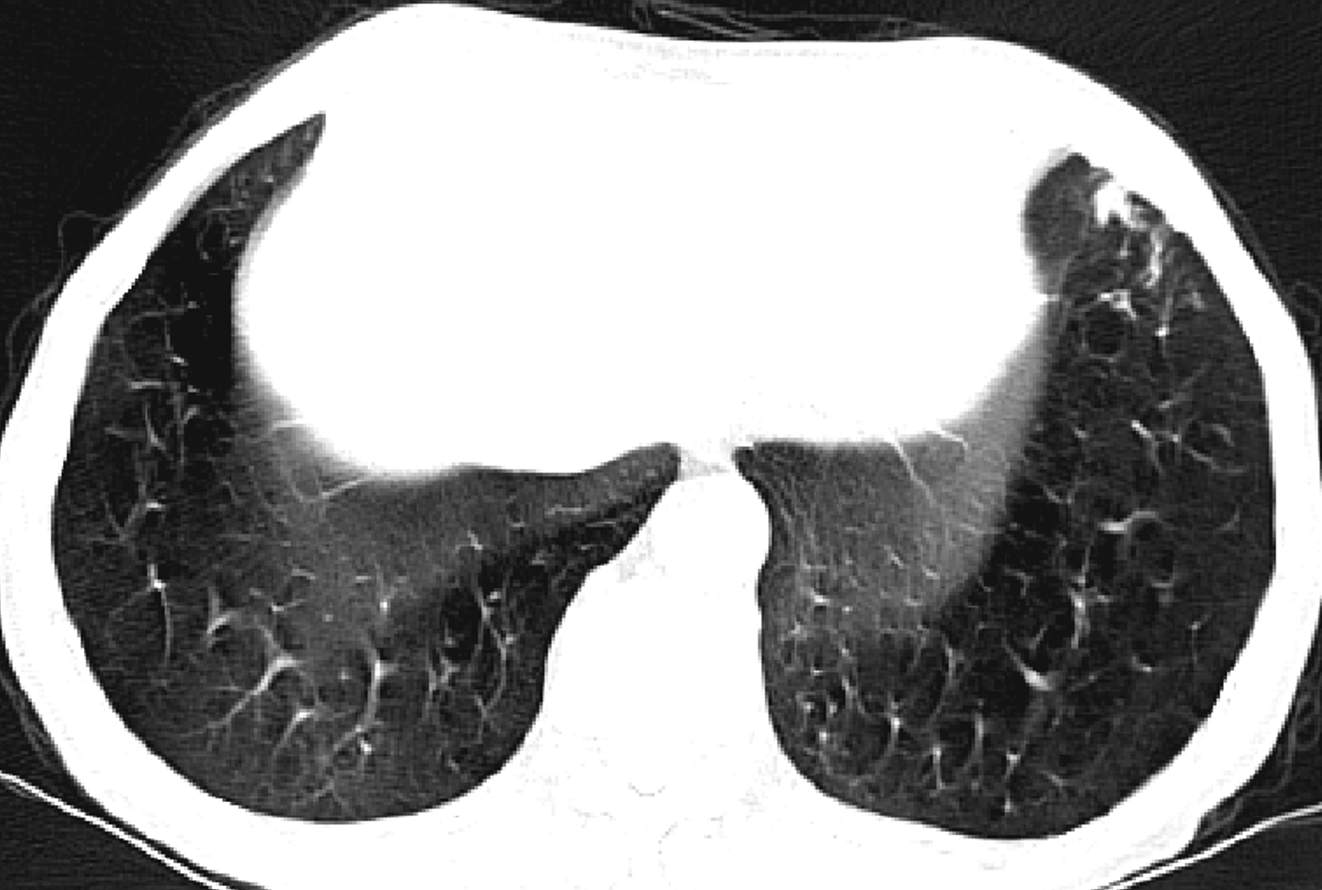

因CT明显异常而复诊。

因患者有肺大泡,肺功能存在一定禁忌。